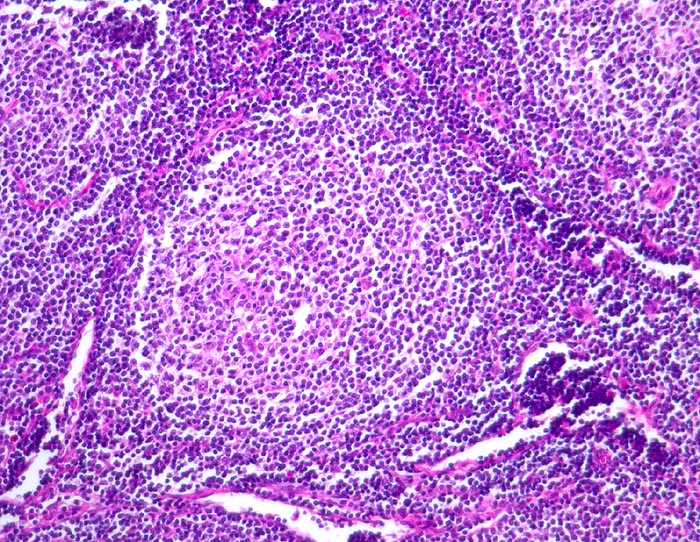

Follikuläres B-Zell Non-Hodgkin-Lymphom

Lymphknoten, abdominal

Neoplastischer Follikel mit unscharfer Begrenzung. Eine dunklere Mantelzone ist nicht erkennbar. Das Follikelzentrum ist auffallend monoton. Es fehlen die Kerntrümmermakrophagen, welche für reaktive Keimzentren typisch sind.

Die Keimzentren sind immunhistochemisch positiv für bcl-2.

Generalisierte Lymphknotenvergrösserung peripher und zentral (abdominal und thorakal). Abgesehen von vergrösserten Lymphknoten keine Symptome.